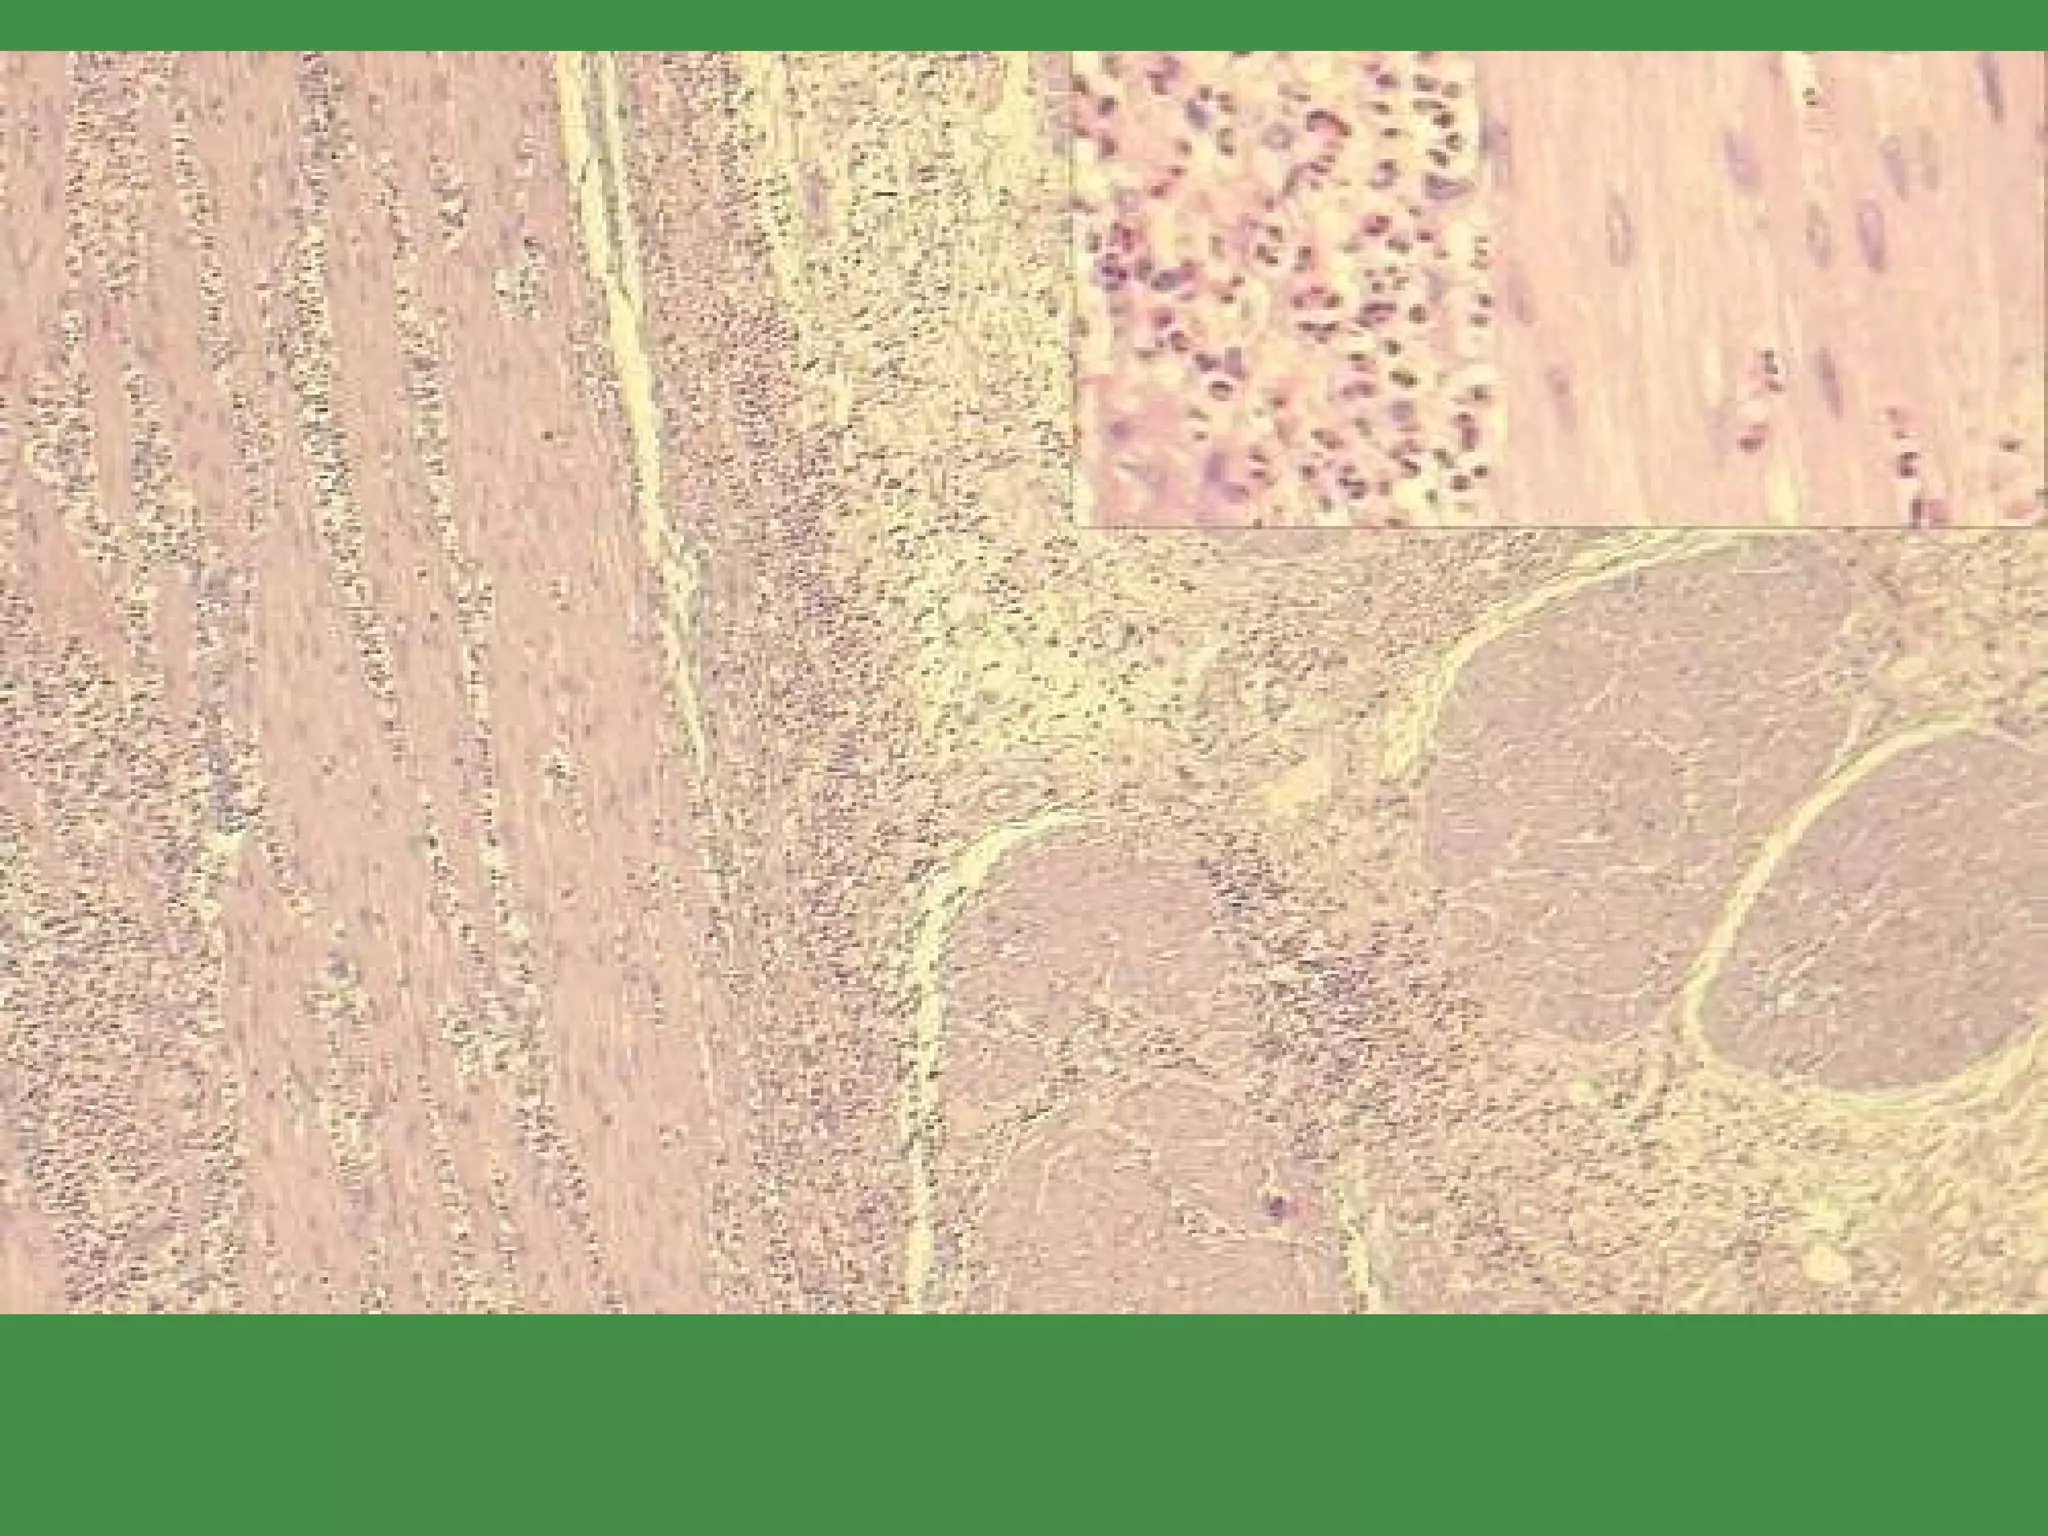

ACUTE APPENDICITIS GENERALLY, a disease of YOUNGER people OBSTRUCTION by FECALITH the classic cause but fecaliths present only about half the time EARLY APPENDICITIS: NEUTROPHILS  Mucosa, submucosa NEED NEUTROPHILS in the MUSCULARIS to confirm the DIAGNOSIS 25% normal rate, usually Perforation  peritonitis the rule, if no surgery

ACUTE APPENDICITIS

ACUTE APPENDICITIS GENERALLY,a disease of YOUNGER people OBSTRUCTION by FECALITH the classic cause but fecaliths present only about half the time EARLY APPENDICITIS: NEUTROPHILS  Mucosa, submucosa NEED NEUTROPHILS in the MUSCULARIS to confirm the DIAGNOSIS 25% normal rate, usually Perforation  peritonitis the rule, if no surgery

• #28 Barrett’s on top, goblet cell on right, normal esophagus on bottom.

• #30 Glandular “dysplasia”